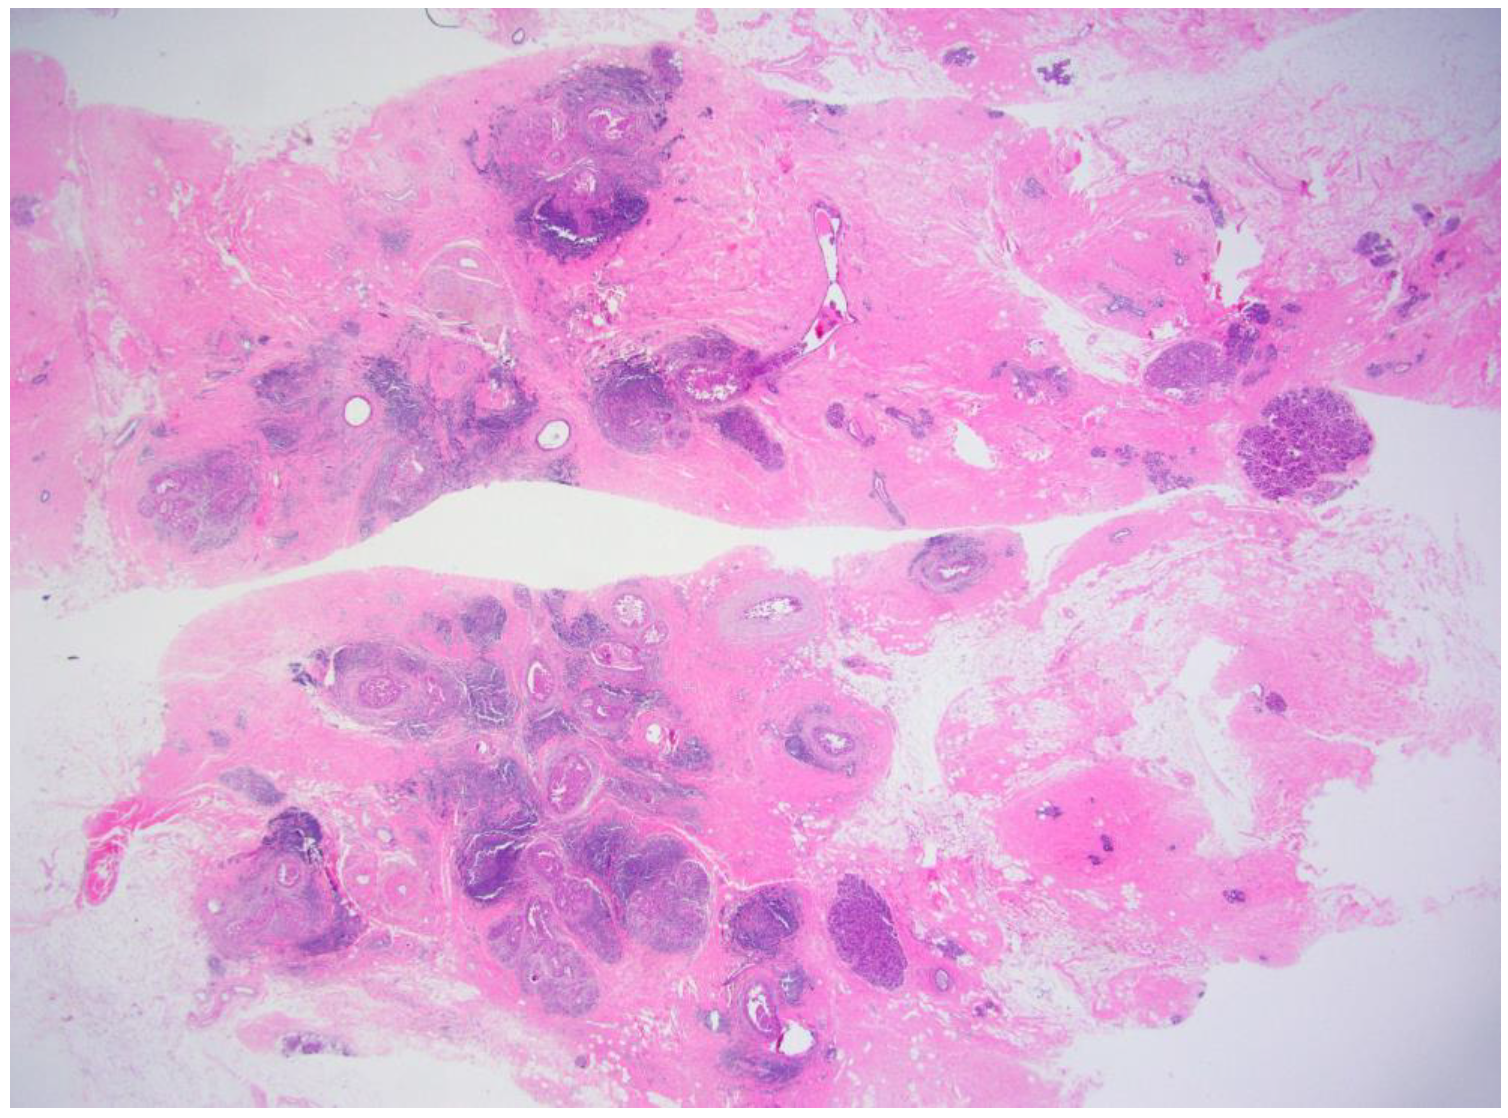

Complete Surgical Excision Is Necessary following Vacuum-Assisted Biopsy for Breast Cancer

3.1. Clincopathological Characteristics of the Study Patients

3.2. Diagnostic Performances of Imaging Modalities for Detecting Remnant Lesions

3.4. The Association of Tumor Size on VABB Specimen and Remnant Tumor on Pathology